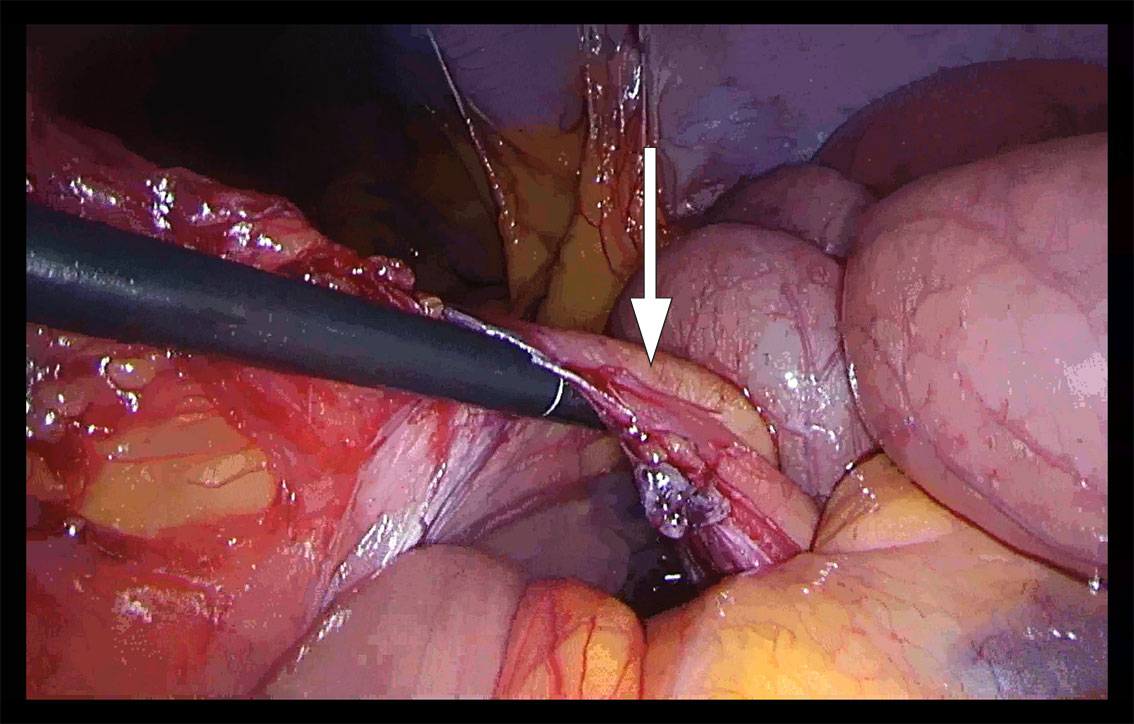

I generell anestesi fant vi ved laparoskopi sparsom fri væske i bukhulen. Store deler av tynntarmen var dilatert. Vi begynte å reponere tynntarmen mot høyre, først fra proksimalt mot distalt og deretter fra ileocøkalovergangen mot proksimalt. Vi fikk inntrykk av at tynntarmen var herniert innunder en «streng» i tilknytning til venstre colon. Ved nærmere ettersyn kunne man skimte vaskulære strukturer, og et tynt og defekt mesenterium kunne ikke utelukkes (figur 1). Grunnet mye dilatert tarm i feltet, begrensede plassforhold og usikkerhet om hvorvidt all tarm var reponert, valgte vi å konvertere til laparotomi. Med midtlinjetilgang fant vi mekanisk tynntarmsileus fra en venstresidig paraduodenal herniering med store deler av tynntarmen herniert mot venstre dorsalt for vena mesenterica inferior. Tynntarmen som ble reponert, framsto som viabel, da det var god tarmmotilitet og god blodsirkulasjon. Det ble satt fortløpende suturer med patent lukning av åpningen i mesenteriet, uten skade av karstrukturene.